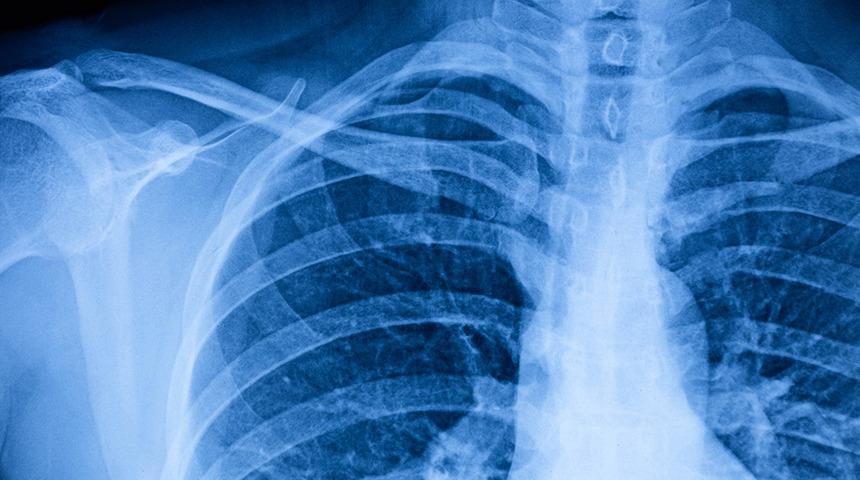

Göğüs duvarı bozuklukları (deformiteleri) doğumdan itibaren görülmeye başlayan, büyüdükçe de belirgin hale gelen ve çocukların psikolojilerini bozan, sosyalleşmelerini engelleyen bir rahatsızlıktır. Deformite tedavisinde farklı yöntemler mevcuttur. Kesin tedavi içinse minimal invaziv cerrahi yöntemler ve gerekli görüldüğünde açık yöntemlerle modifiye şarttır. Bunlar yüz güldürücü sonuçları beraberinde getirir.

Konu ile ilgili bilgi veren Göğüs Cerrahisi Uzmanı Doç. Dr. Özkan Demirhan,” Birçok göğüs duvarı deformitesi olmasına rağmen biz en sık görülen Kunduracı Göğüs ( Pektus ekskavatum ) ve Pektus karinatumdan (Güvercin Göğsü) bahsedeceğiz. Kunduracı göğüs, çocuklarda en sık görülen göğüs duvarı bozukluğudur. Göğüs çöküklüğünün muhtemel nedeni tam olarak bilinmese de teori olarak kaburgaların büyüme esnasında sternumun (İman tahtasını) özellikle alt orta kısmını içe doğru çöktürmesinden kaynaklanmaktadır. Genellikle doğumda veya yaşamın ilk yıllarında ortaya çıkar. 14 -15 yaşlarındaki hızlı büyüme döneminde, mevcut olan deformite daha belirgin hale gelir. Her 300 – 400 doğumda bir oranında görülmektedir. Erkeklerde kadınlara göre 4 kat daha sık rastlanır ve ailesel yatkınlık söz konusudur. Yüzde 20 oranında diğer kas iskelet anomalileri ile birlikte görülebilir. Doğumsal bir anomali olduğu için doğumsal kalp hastalıkları ile beraber de görülebilir.” dedi.

Kunduracı göğüste meydana gelen şikayetlere değinen Demirhan,” Bu hastalarda en sık görülen şikayet kozmetik bozukluk, buna bağlı depresyon ve sosyalleşmede zayıflık görülür. Örneğin plajda ve havuzda hiç pektus ekskavatumlu kişilerin yüzdüğüne rastlamayız. Nadir de olsa nefes darlığı, göğüs ağrısı, çarpıntı ve efor kapasitesinin düşük olması da diğer şikayetlerdir. Şikayetler Pektus ekskavatum yenidoğanlarda ve çocuklarda iyi tolere edilir. Gelişen semptomlar deformitenin derecesi ile ilgilidir. Hafif göğüs çökmesi durumlarında genelde hiçbir şikayet görülmez. Semptomlar genellikle büyümenin hızlı olduğu erken ergenlik döneminde başlar. Orta ve ileri çöküntülerde; eforla gelen çarpıntı, şiddetli göğüs ağrısı, nefes darlığı, çabuk yorulma, siyanoz, bayılma, taşikardi gibi semptomlar görülebilir. İleri düzeydeki deformitelerde egzersiz toleransı genelde düşüktür, bazı hastalarda sık tekrarlayan akciğer enfeksiyonları görülmektedir. Özellikle ileri yaştaki hastaların yüzde 10'unda egzersiz sonrası deformitenin olduğu bölgede ağrı gözlenir. Öte yandan Pektus Karinatum konjenital göğüs duvarı deformiteleri arasında Pektus Ekskavatum'dan sonra en sık görülen deformitedir. Pektus karinatum halk dili ile güvercin göğüs olarak adlandırılır. Göğüs ön duvarının öne doğru çıkıntı yaptığı deformite şeklidir. Ekskavatumun aksine bu da kaburgalar gelişim esnasında sternumu öne doğru iterler. 10 bin doğumda bir görülür. Erkeklerde 4 kat daha fazladır. Doğumda tanımlanmasına rağmen çoğu orta çocukluk (11-15 yaşlarında) döneminde daha belirginleşerek ortaya çıkar. Hastaların yüzde 25'inde aile öyküsü vardır. Hastalığa en sık eşlik eden deformite skolyoz yani omurga eğriliğidir. Diğer doğumsal anomaliler nadirde olsa eşlik edebilir. Bu hastalarında en çok şikayeti kozmetik ve buna bağlı psikolojik sorunlardır. Bunlarda sosyalleşmekten çekinen içine kapanık insanlardır. Nadir de olsa bazı hastalarda göğüs ağrısı, eforla gelen nefes darlığı olabilmektedir.” ifadelerini kullandı.